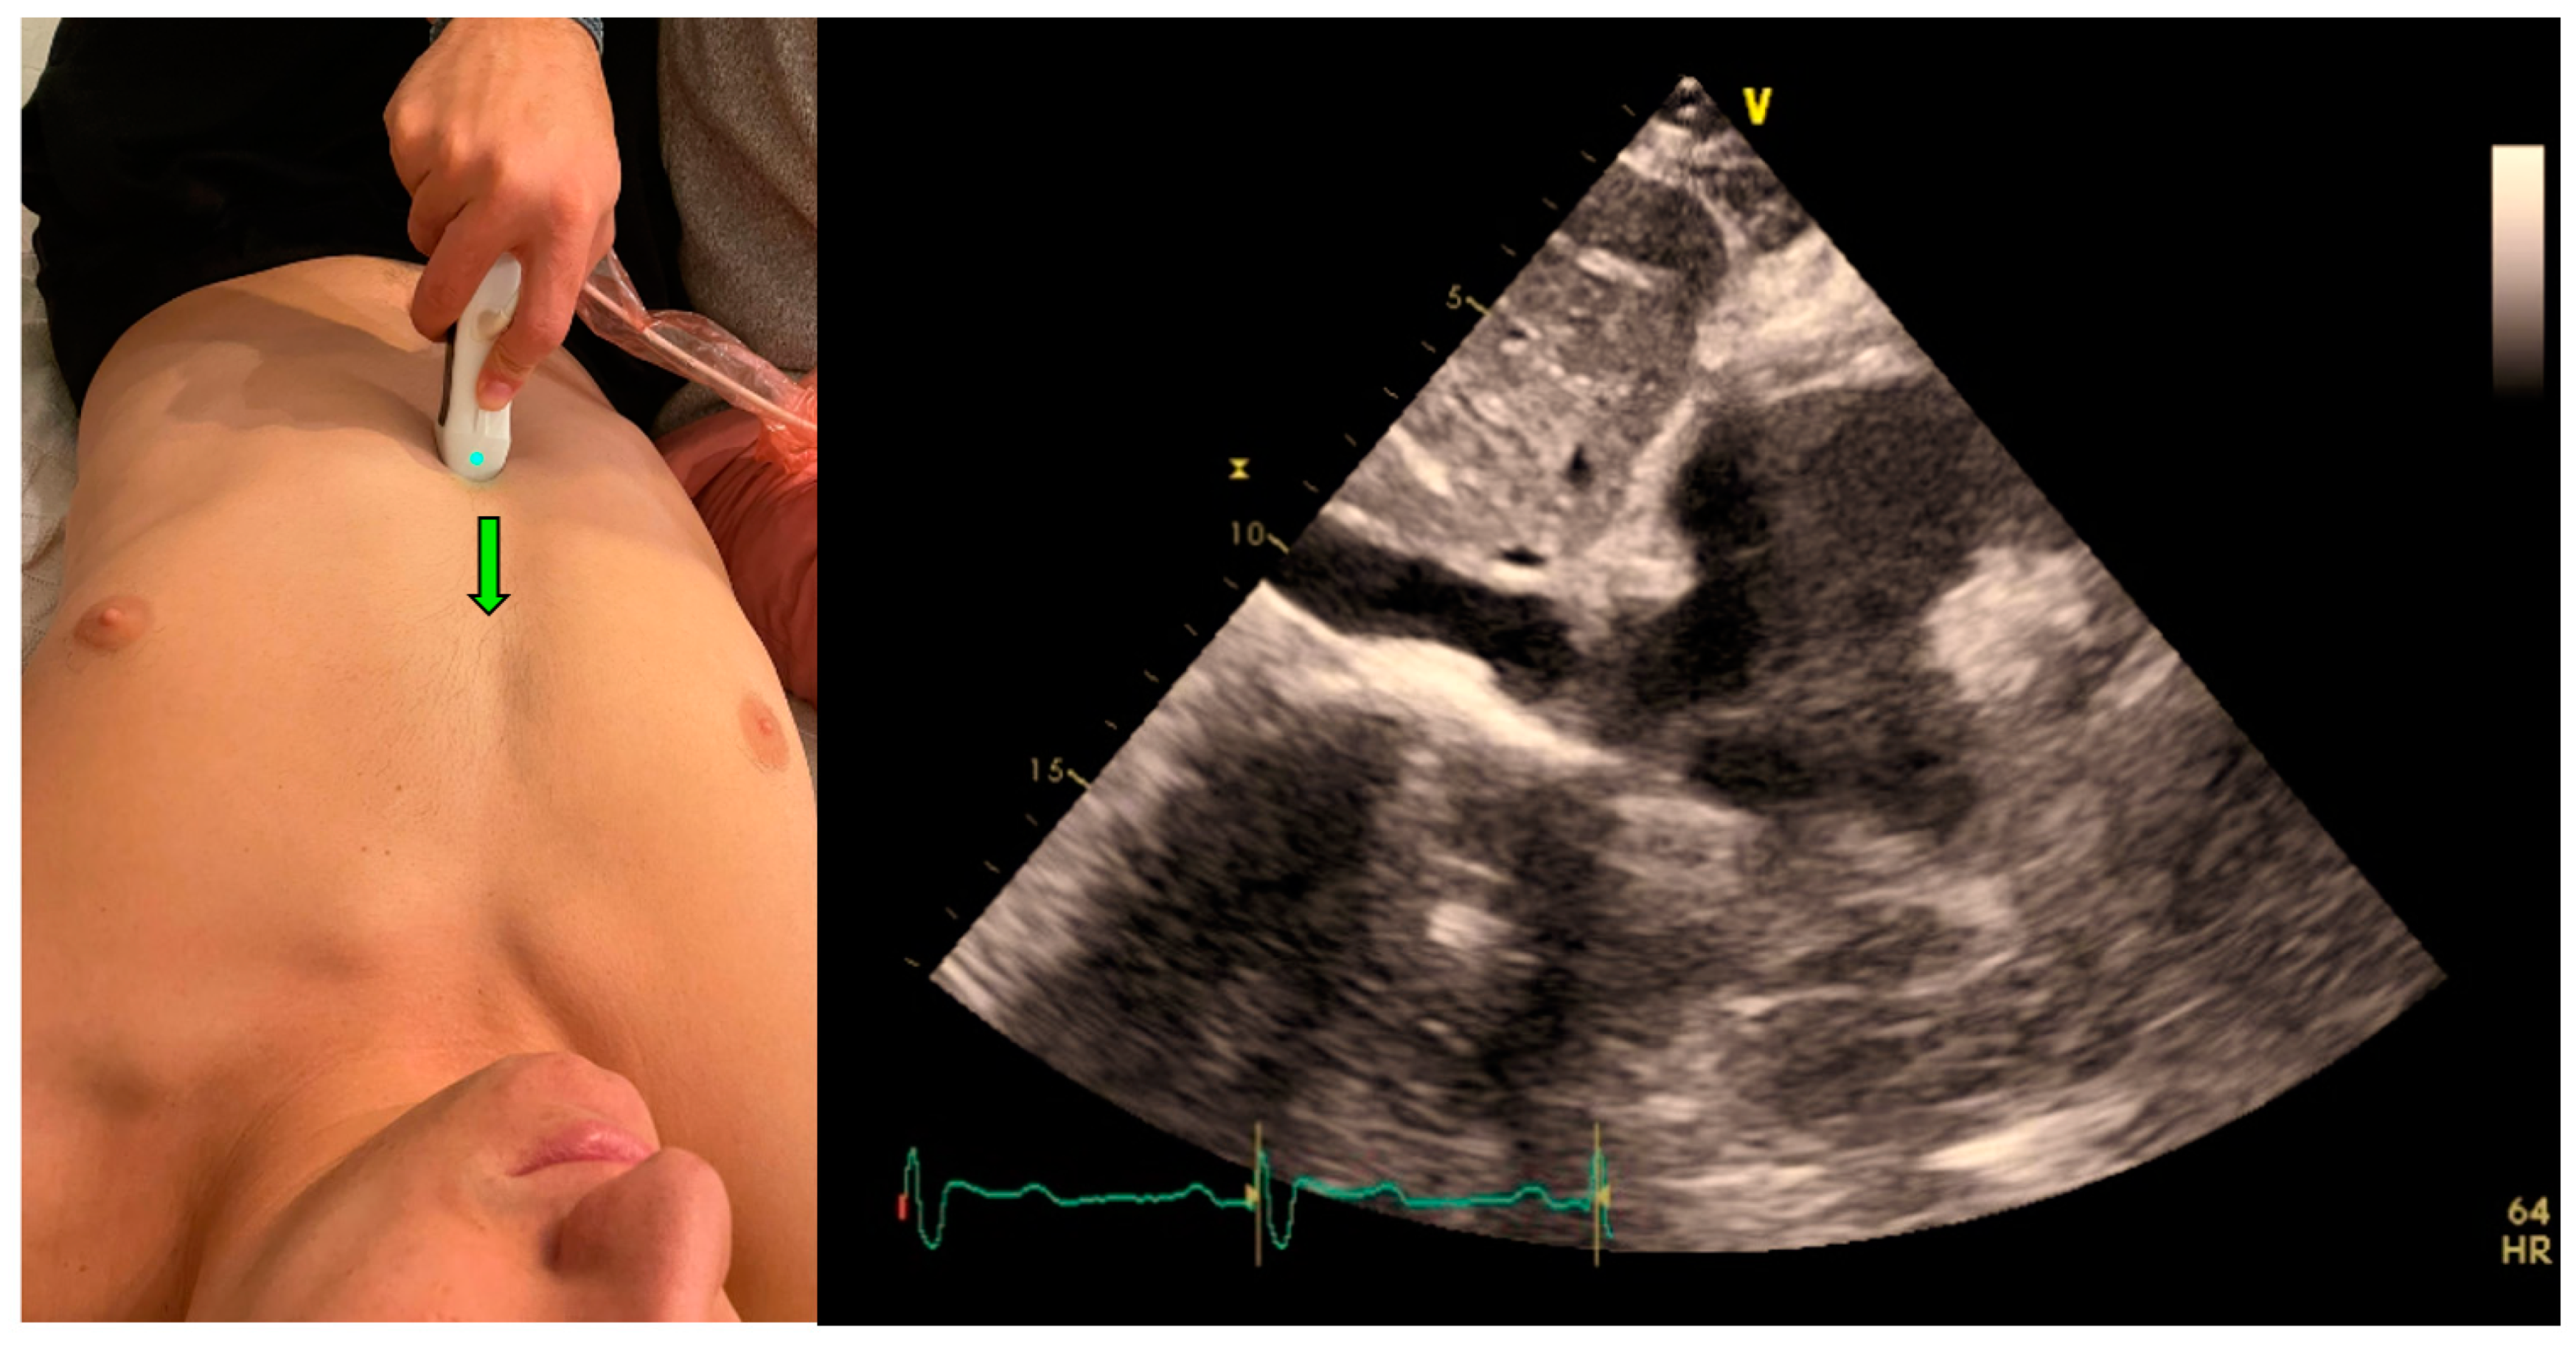

The IVC clips were taken from the subcostal IVC view (Figure 3). In this view, the maximum and minimum diameters of the IVC throughout a respiratory cycle were measured two cm from the IVC-right atrium junction, using M-mode, providing the CI that represents the collapsibility of the IVC.

As mentioned, all clips were scored manually based on the quality of imaging from zero to two: 0—low, or failed attempt to track the IVC, or image that could not be analyzed, 1—CI can be measured and calculated but with moderate imaging quality and 2—for good quality clips with a clearly demonstrated IVC.

Figure 3. Acquisition (probe point—green arrow) and anatomy of IVC View.